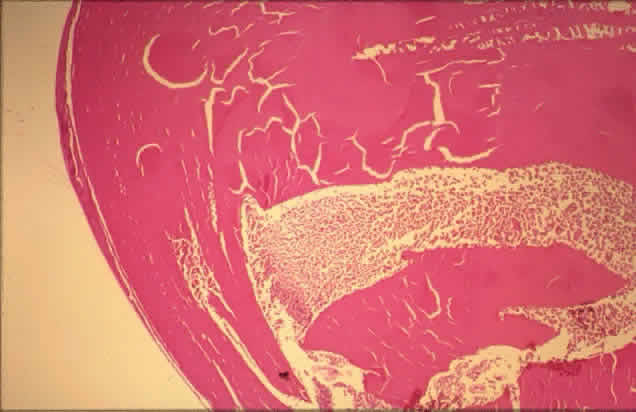

Histologically, new vessels develop between the retinal surface and the posterior surface of the formed vitreous (Fig. 12). With NVE, there is a demonstrable break through the internal limiting membrane (Fig. 13).20 Early-developing new vessels have lumina even at the proliferating tips.53 Active new vessels have endothelial cells and pericytes, with fenestrations. Morphologically, fenestrations are areas ranging from 40 to 80 nm in diameter where the cell membranes are focally fused, and are normal findings in capillaries outside of the retina and brain. They allow increased permeability and are responsible for the diffuse leakage of fluorescein seen from new vessels on angiography. Inactive or “ghost” new vessels are acellular, having lost both endothelium and pericytes.39 With time, fibrous tissue develops and accompanies the new vessels. The vessels themselves may leak and bleed into the vitreous, leading to visual loss.

Fig. 12. Neovascularization at the disc with fibrous proliferation. The fibrovascular membrane overlies the internal limiting membrane, which is wrinkled (arrows). The retinal detachment is artifactual. (PAS, × 19.5)